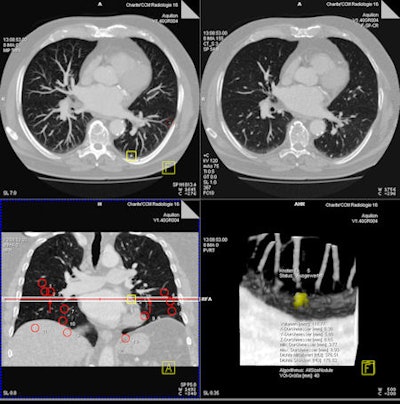

| Above, axial CT image in standard-dose CT (SD-CT) showing a nodule in juxtadiaphragmatic location missed by CAD-1. Above right, CAD markers resulting from the analysis of the SD-CT data presented in a coronal view. Below, CAD analysis of the ultralow-dose CT (ULD-CT) data resulted in automated detection of the corresponding nodule in the left lower lobe. On the right, CAD markers resulting from the analysis of the ULD-CT data. All images courtesy of Dr. Valentina Romano. |

The group compared the results of CAD analysis by assessing detection sensitivity and false-positive detections with ultralow-dose CT (ULD-CT) and standard-dose CT (SD-CT) protocols. Data were collected on 26 patients with known lung cancers.

CT images were consecutively acquired at 5 mAs (ULD-CT) and 75 mAs (SD-CT) with 120 kV tube voltage and 1-mm slice thickness. Images were examined using a soft-tissue kernel as recommended by the manufacturers.

The sensitivity results for both systems did not decline significantly for standard-dose protocols versus low-dose settings: for SD-CT and ULD-CT, respectively, the sensitivity for detecting nodules 4 mm and larger was 72% and 73% for the CAD-1 application and 62% and 56% for CAD-2.